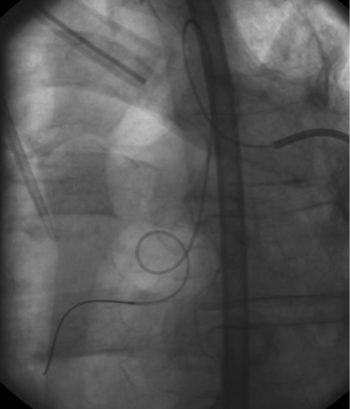

Angiografiebild: Zu erkennen ist ein Koaxialkatheter in der gewundenen Bronchialarterie.